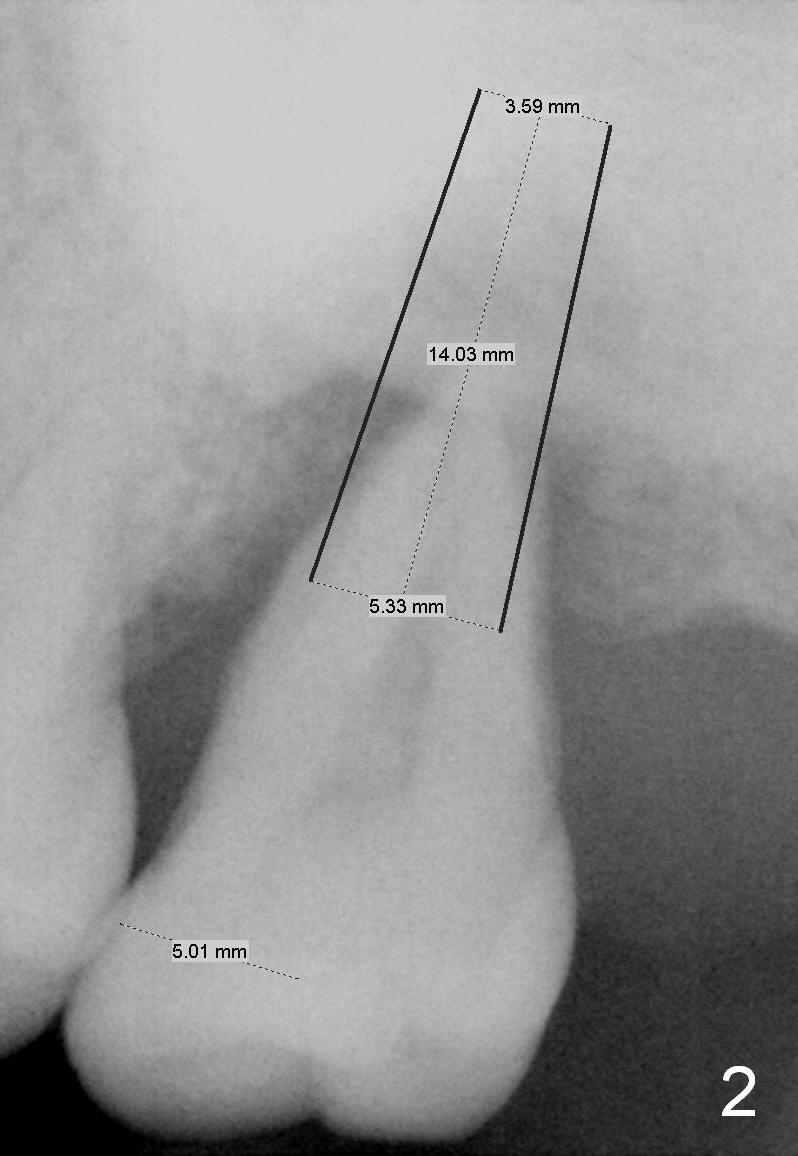

A 49-year-old lady has history of periodontal disease (Fig.1). The teeth #2 and 19 have been extracted and replaced by immediate implants. When she returns, crown is going to be cemented at #19 and delayed implant will be placed at #15. The tooth was extracted 4.5 years ago. No PA has been taken since extraction. Fig.2,3 show design for immediate implant if the tooth were not extracted (*: mesial crest; O: bone graft). Note the orientation of the implant and the space from the neighboring tooth.